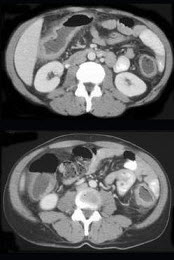

女,55岁,腹胀,肛门闭气,消瘦乏力,肝区疼痛,CT检查如图,最可能的诊断为( )

A:多发性肝脓肿

B:肝癌肝内转移

C:肝淋巴管瘤

D:肝脏囊腺瘤

E:结肠癌肝转移